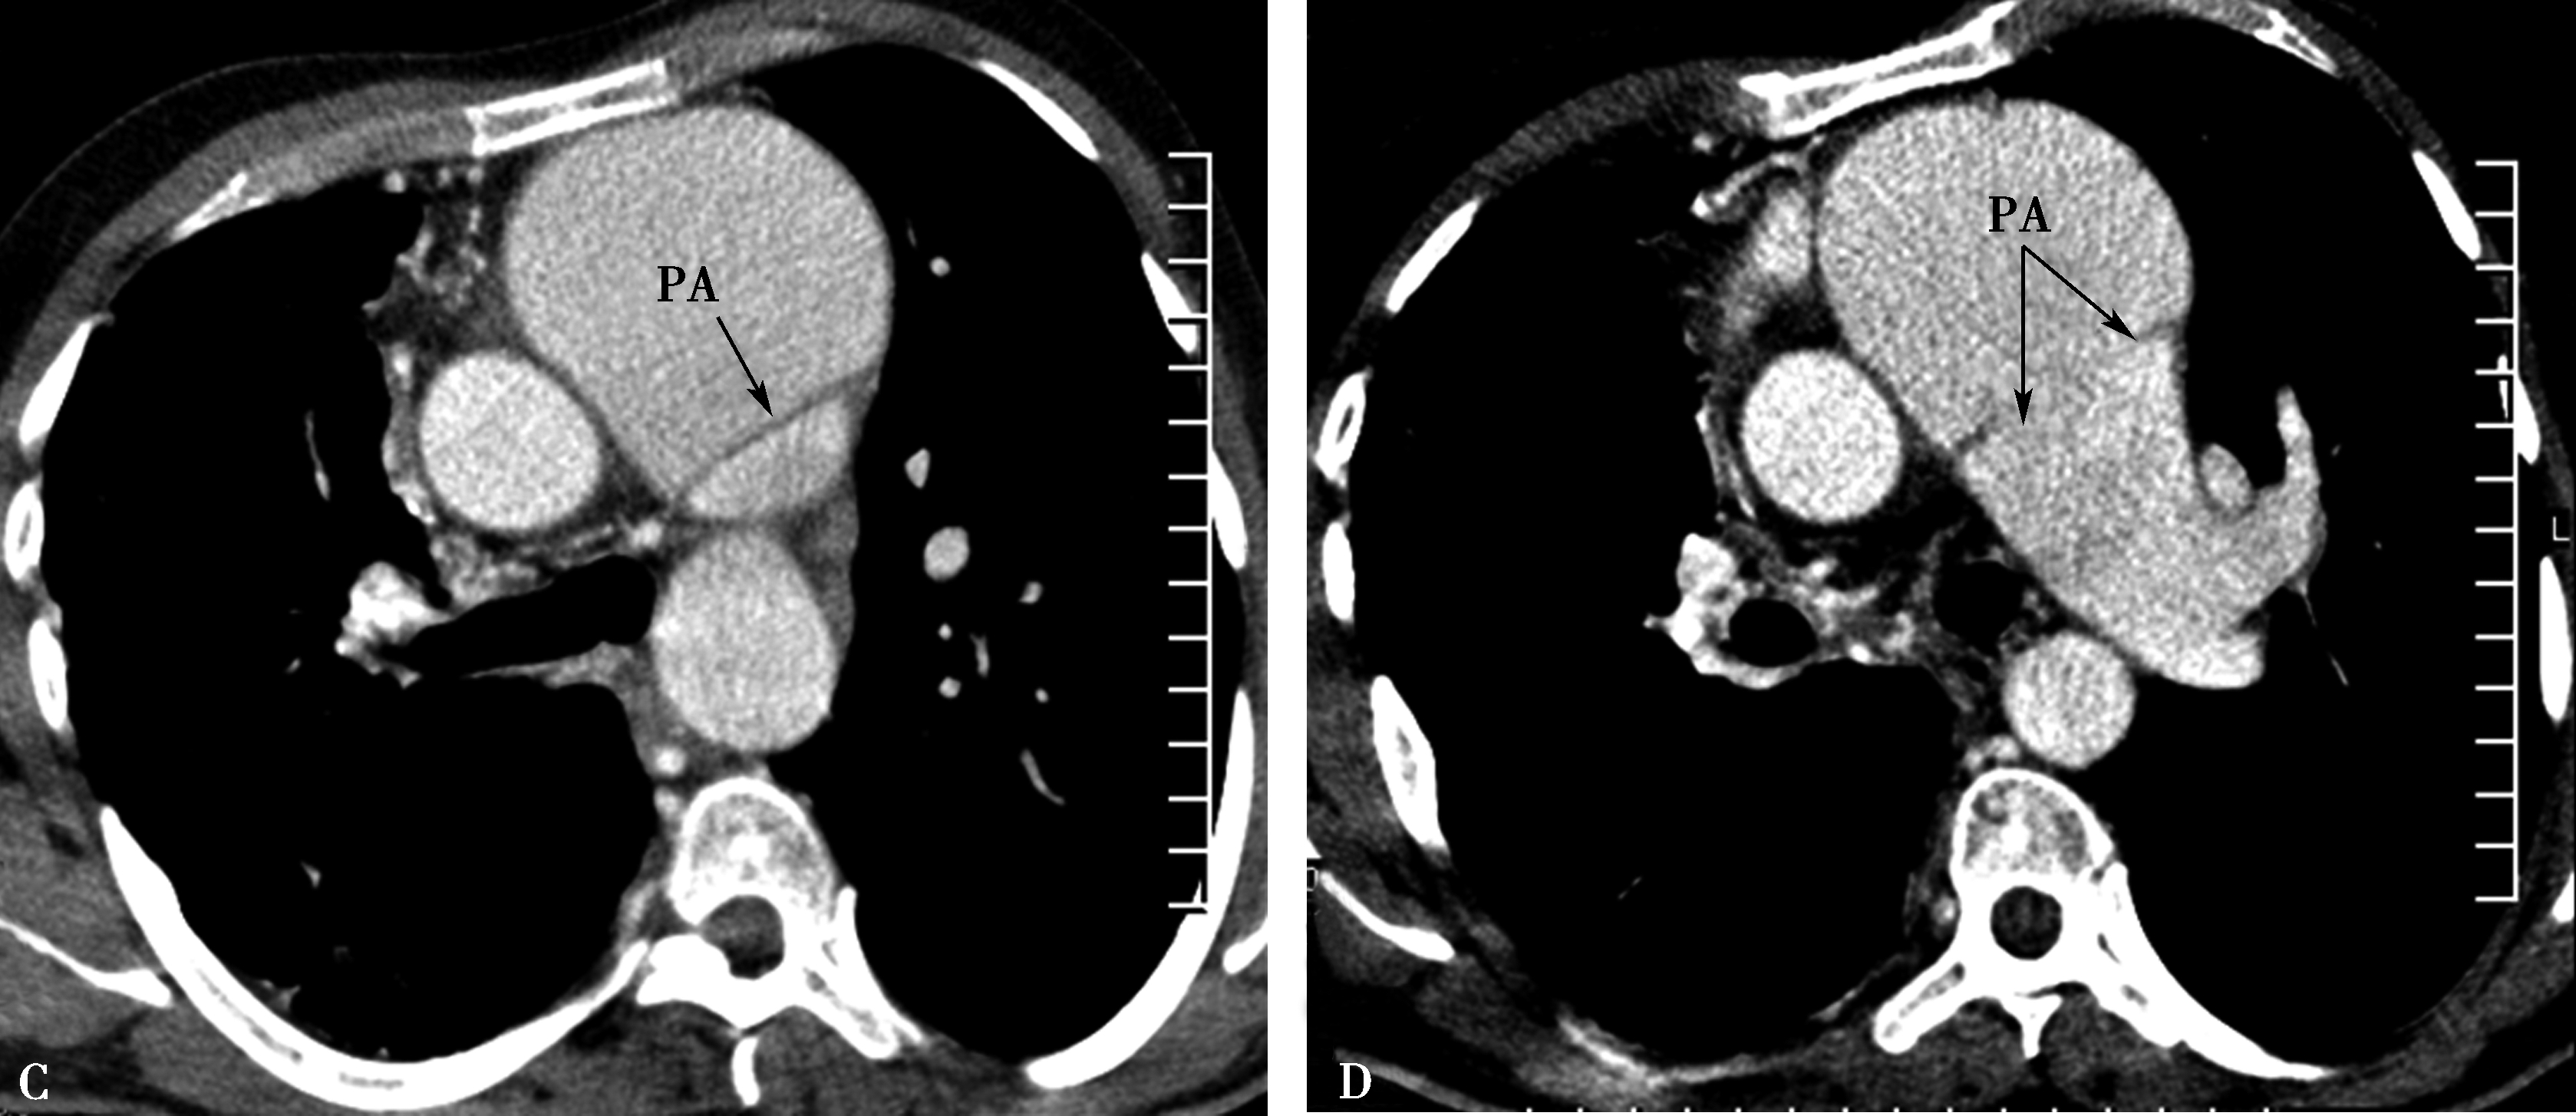

肺动脉受累表现为主肺动脉及左右肺动脉外形不规则,粗细不均,不同程度狭窄-闭塞、与瘤样扩张交替出现;管壁钙化;可以出现肺动脉高压征象,右心房室扩大(图8-6-1,图8-6-2)。

图8-6-1 缩窄性心包炎、纵隔炎(结核性),心包缩窄术后

A、B.横断图像,右肺动脉被纵隔纤维化包围重度狭窄-闭塞(A↑);右侧肺血少(B↑),左侧肺血多(B↑);肺动脉高压,右心房扩大。AO:升主动脉;PA:肺动脉;RPA:右肺动脉;LPA:左肺动脉

图8-6-2 男,34岁,慢性纵隔炎(结核性)肺动脉、主动脉受累,肺动脉高压

A、B.横断扫描纵隔增宽,纵隔胸膜增厚,主动脉与肺动脉间低密度脂肪间隙消失,代之以中等密度(结缔组织),主动脉、主肺动脉及左右肺动脉外形不规则,粗细不均,钙化。主肺动脉及右肺动脉狭窄为主,左肺动脉瘤样扩张;C、D.肺动脉三维重建,示主肺动脉及右肺动脉粗细不均,不规则狭窄,主肺动脉瘤扩张。PA:主肺动脉;LPA:主肺动脉;RPA:右肺动脉;AO:升主动脉